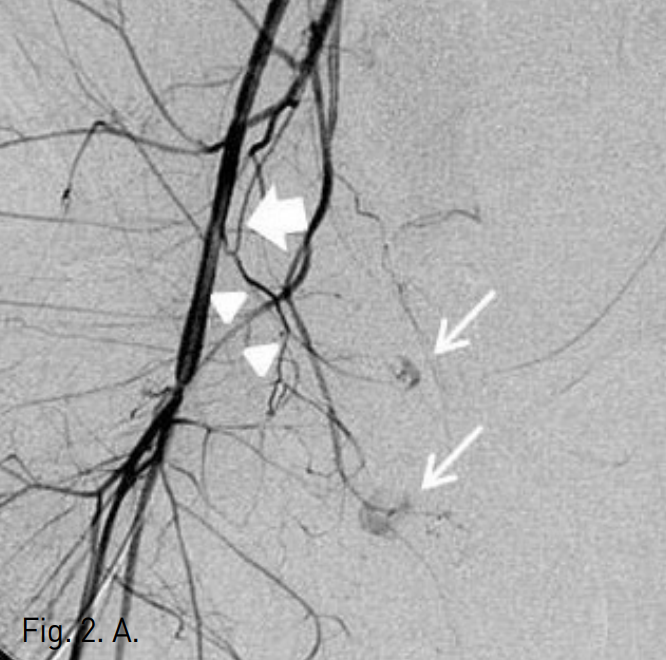

To identify the location of the bleeding site, digital subtraction angiography was performed. Selective angiogram of right common iliac artery showed two contrast extravasations or bleeding points at suprapubic area(Fig. 2A). Selective internal iliac arteriogram showed only one bleeding point from the obturator artery(Fig. 2B). After superselective cannulating into the feeding branch from the obturator artery by using a coaxial microcatheter, embolization was performed with gelfoam particles(Fig. 2C). Follow-up right common iliac angiogram showed persistent contrast extravasation and identified feeding branch of aberrant obturator artery from the inferior epigastric artery(Fig. 2D). Additional selective embolization was performed with gelfoam particles.

Fig. 2

A. Pelvic angiogram shows two contrast extravasations in pubic area (thin arrows). The inferior epigastric artery (thick arrow) and aberrant obturator artery (arrowheads) are noted.

B. Internal iliac arteriogram shows active bleeding from the obturator artery (arrow).

C. Selective embolization of obturator artery from the internal iliac artery was done.

D. Persistent contrast extravasation being fed by aberrant obturator artery (arrows), a branch of inferior epigastric artery, is identified on common iliac angiogram. So additional selective bleeding artery embolization was done.